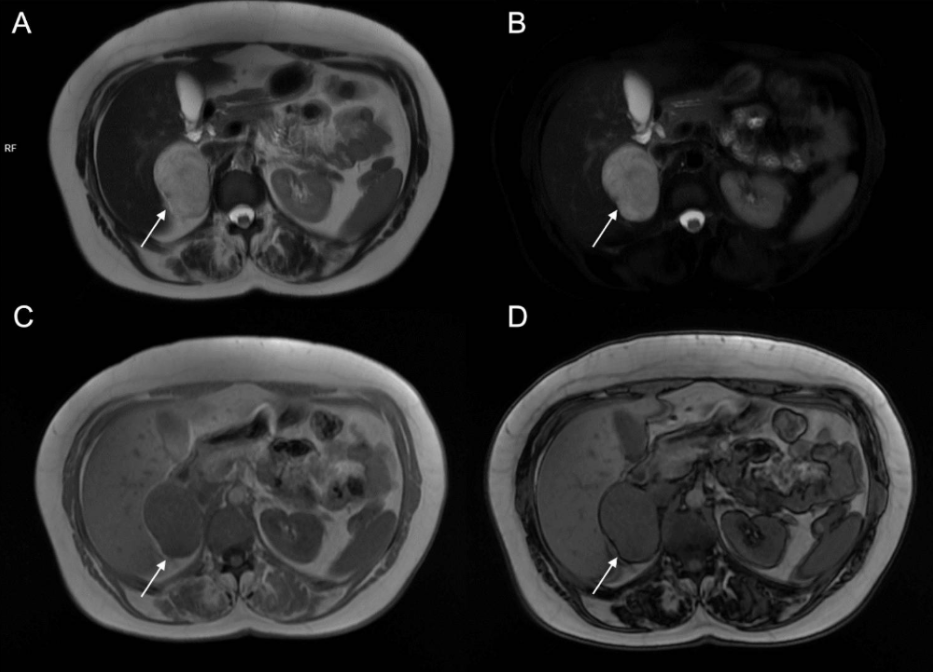

Signal Drop on Out-of-Phase Imaging: This is a technical phrase used by radiologists. It means that, when certain MRI pictures are taken (so-called “out-of-phase” images), the spot becomes less visible or darker, which is a classic sign of a fat-rich (lipid-rich) adenoma, and usually points toward a benign lump17.

This is a common, harmless lump that usually doesn’t cause symptoms. On MRI, they show a characteristic loss of signal on special out-of-phase sequences because the fat cancels out the signal from water20. This helps distinguish them from other tumours. They usually appear small, smooth, and uniform.

A benign mass that contains little or no fat, so they do not show the typical signal loss on out-of-phase MRI21. They can be harder to tell apart from malignant tumours because their MRI appearance is less specific. Their shape is usually well-defined but may vary.